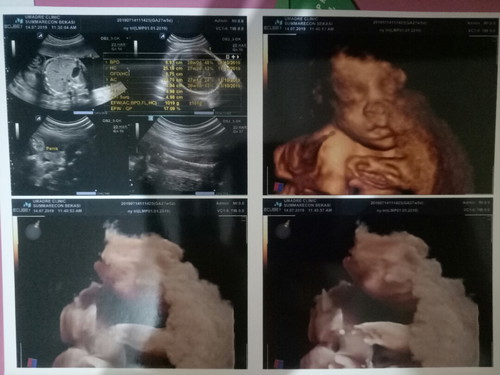

usg

Allhamdulillah.. Sehat2 terus sayang. ??